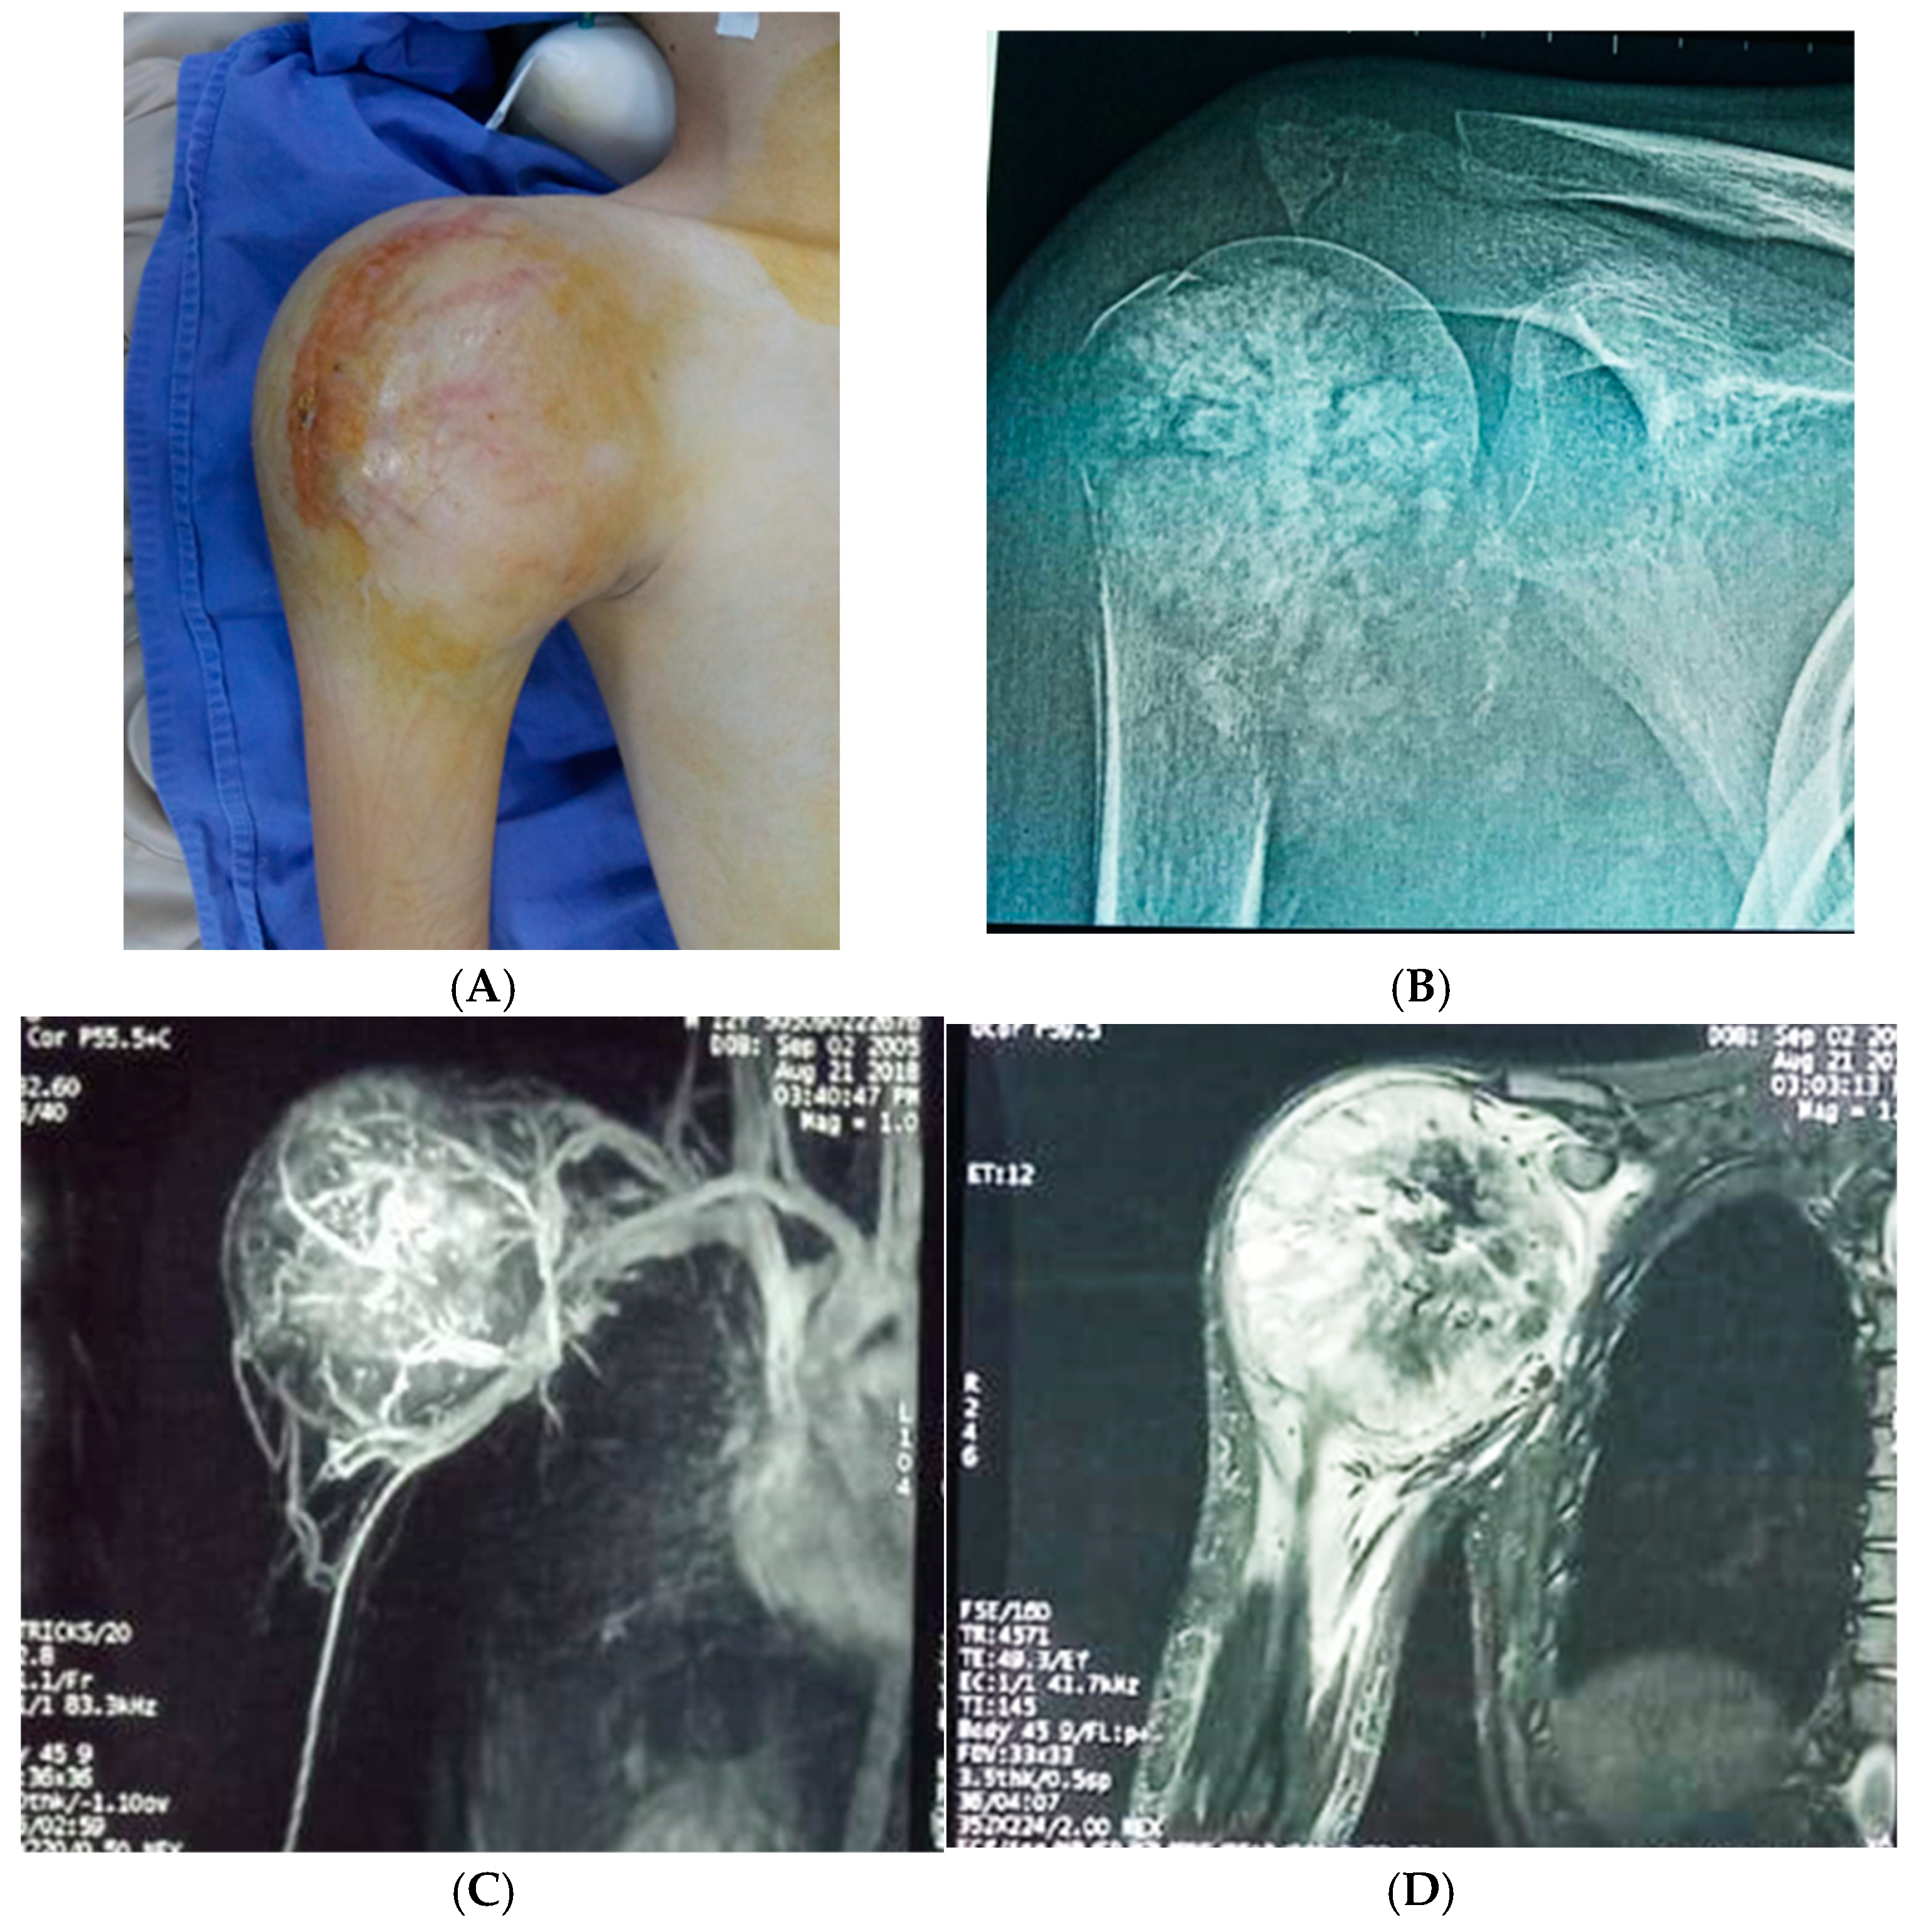

For the studied group, the main symptoms at presentation were attributed by the patient and relatives to trauma. The main symptoms were pain (93.8%), functional impotence (87.7%) and swelling (100%). Figure 2, Figure 3 and Figure 4 present the clinical, imaging and intra-operative appearance of the humeral and femoral OS for two of our patients.

Figure 3. Resection piece containing humeral tumour, proximal half of the humerus, part of the scapula and clavicle—Patient in Figure 2.